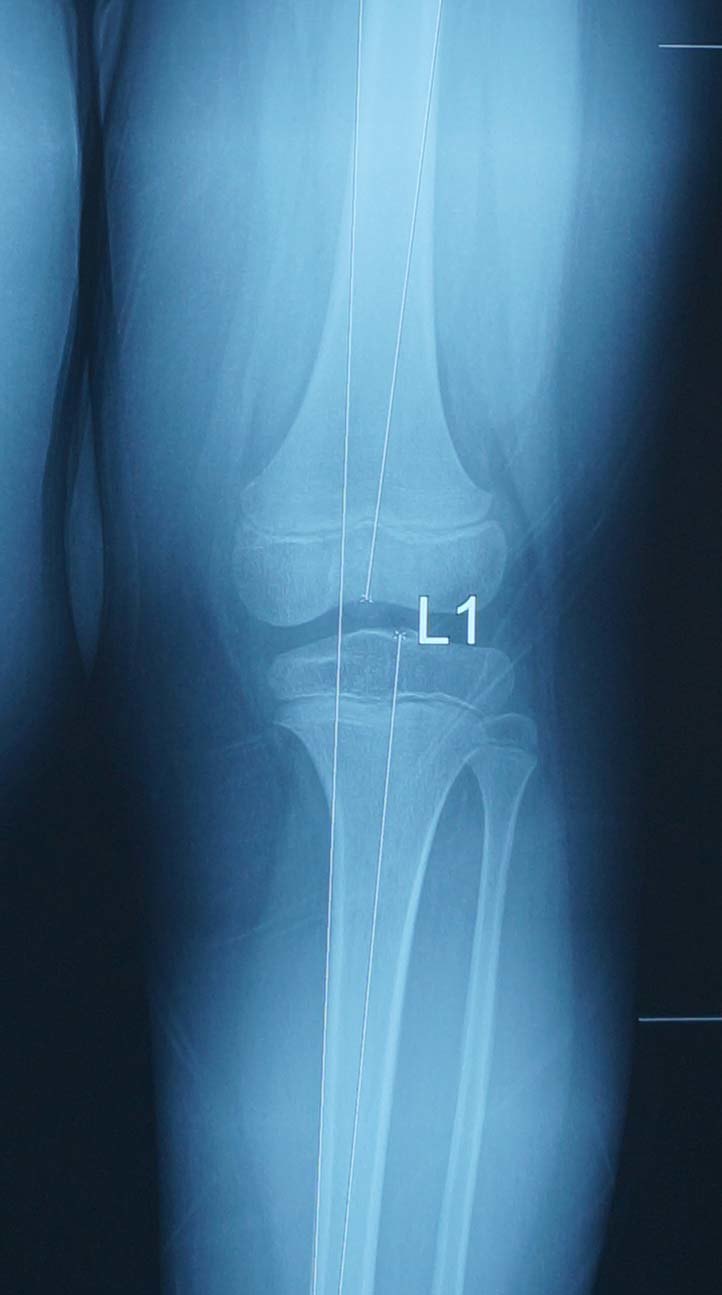

1.概念 很多病友不知道医学上什么叫膝内、外翻,所以往往把两者搞反。病友往往认为膝盖部位向外侧突出就叫膝外翻,而膝盖向内侧突出就叫膝内翻,其实正好相反。医学术语把膝盖往外侧突出叫膝内翻,往内侧突出叫膝外翻。之所以如此定义,是因为医学上,膝内外翻是指下肢力线(医学术语叫机械轴,是髋关节中心和踝关节中心的连线)相对于膝关节中心的位置,力线位于膝关节中心的外侧叫膝外翻,位于内侧叫膝内翻。

膝内翻